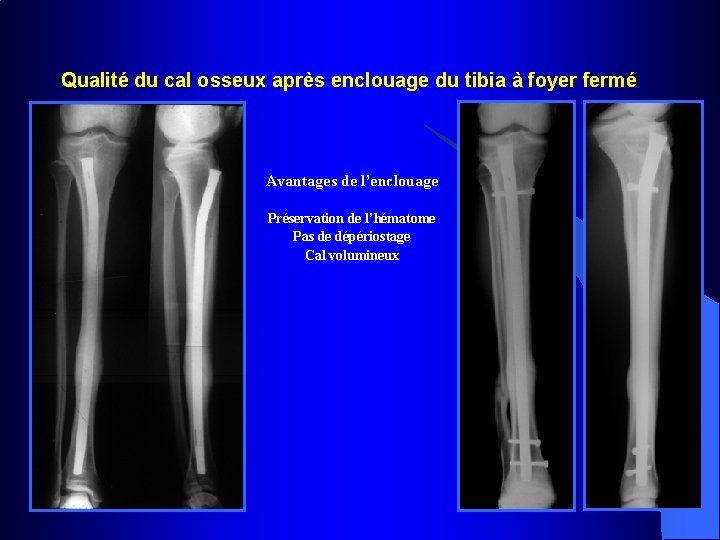

Cal après enclouage du tibia à foyer fermé Avantages de l’enclouage Préservation de l’hématome Pas de dépériostage Cal volumineux

Qualité du cal osseux après enclouage du tibia à foyer fermé Avantages de l’enclouage Préservation de l’hématome Pas de dépériostage Cal volumineux

Clou à foyer fermé verrouillé Vis enlevées à 3 mois Guérison 6 mois